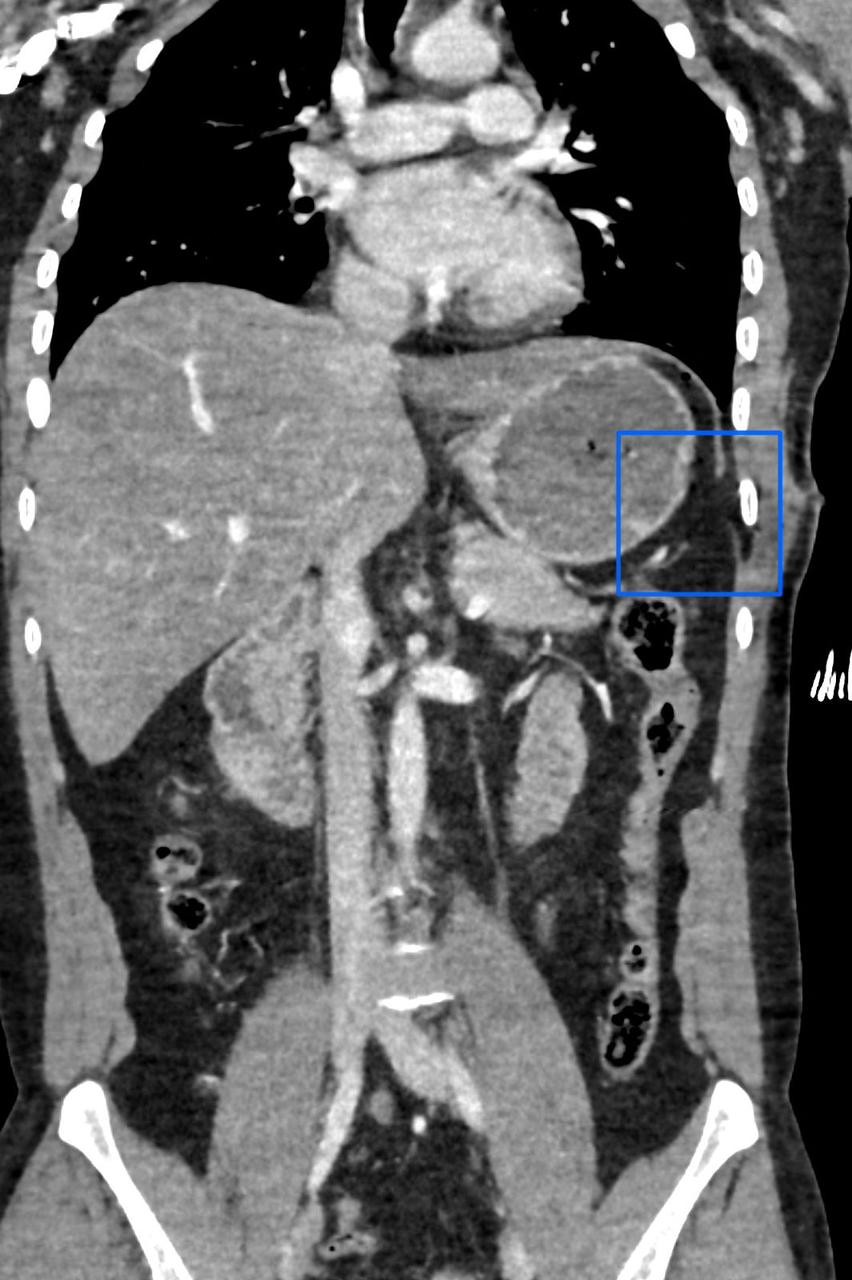

تمكن مستشفى الإيمان العام عضو تجمع الرياض الصحي الأول من إنقاذ حياة شاب عشريني تعرض لإصابة في الجهة اليسرى من الصدر؛ أدت إلى حدوث قطع في الحجاب الحاجز، وثقب في القولون المستعرض.

حيث قام الفريق الطبي بقيادة رئيس قسم الجراحة العامة استشاري الجراحة والمناظير د. سعد الدوسري، واستشاري الجراحة العامة د. ريان الحوشان بإجراء جراحي عاجل تم خلاله إصلاح الإصابات المذكورة عن طريق المنظار الجراحي عبر ثلاثة فتحات صغيرة بحجم 5 مم، تكللت بالنجاح -ولله الحمد-.

الجدير بالذكر أن مثل هذه الإصابات عادة يتم إجراؤها عن طريق الشق الكامل للبطن، ولكن إستطاع الفريق الطبي بمستشفى الإيمان العام تفاديه -بتوفيق من الله-؛ حيث ساهمت خبرة الفريق الطبي وتوفر الإمكانيات والتقنيات الحديثة في المستشفى من إجراء العملية وفق أفضل الممارسات الطبية والتي ساهمت بتحسن حالة المريض في فترة وجيزة -ولله الحمد-.